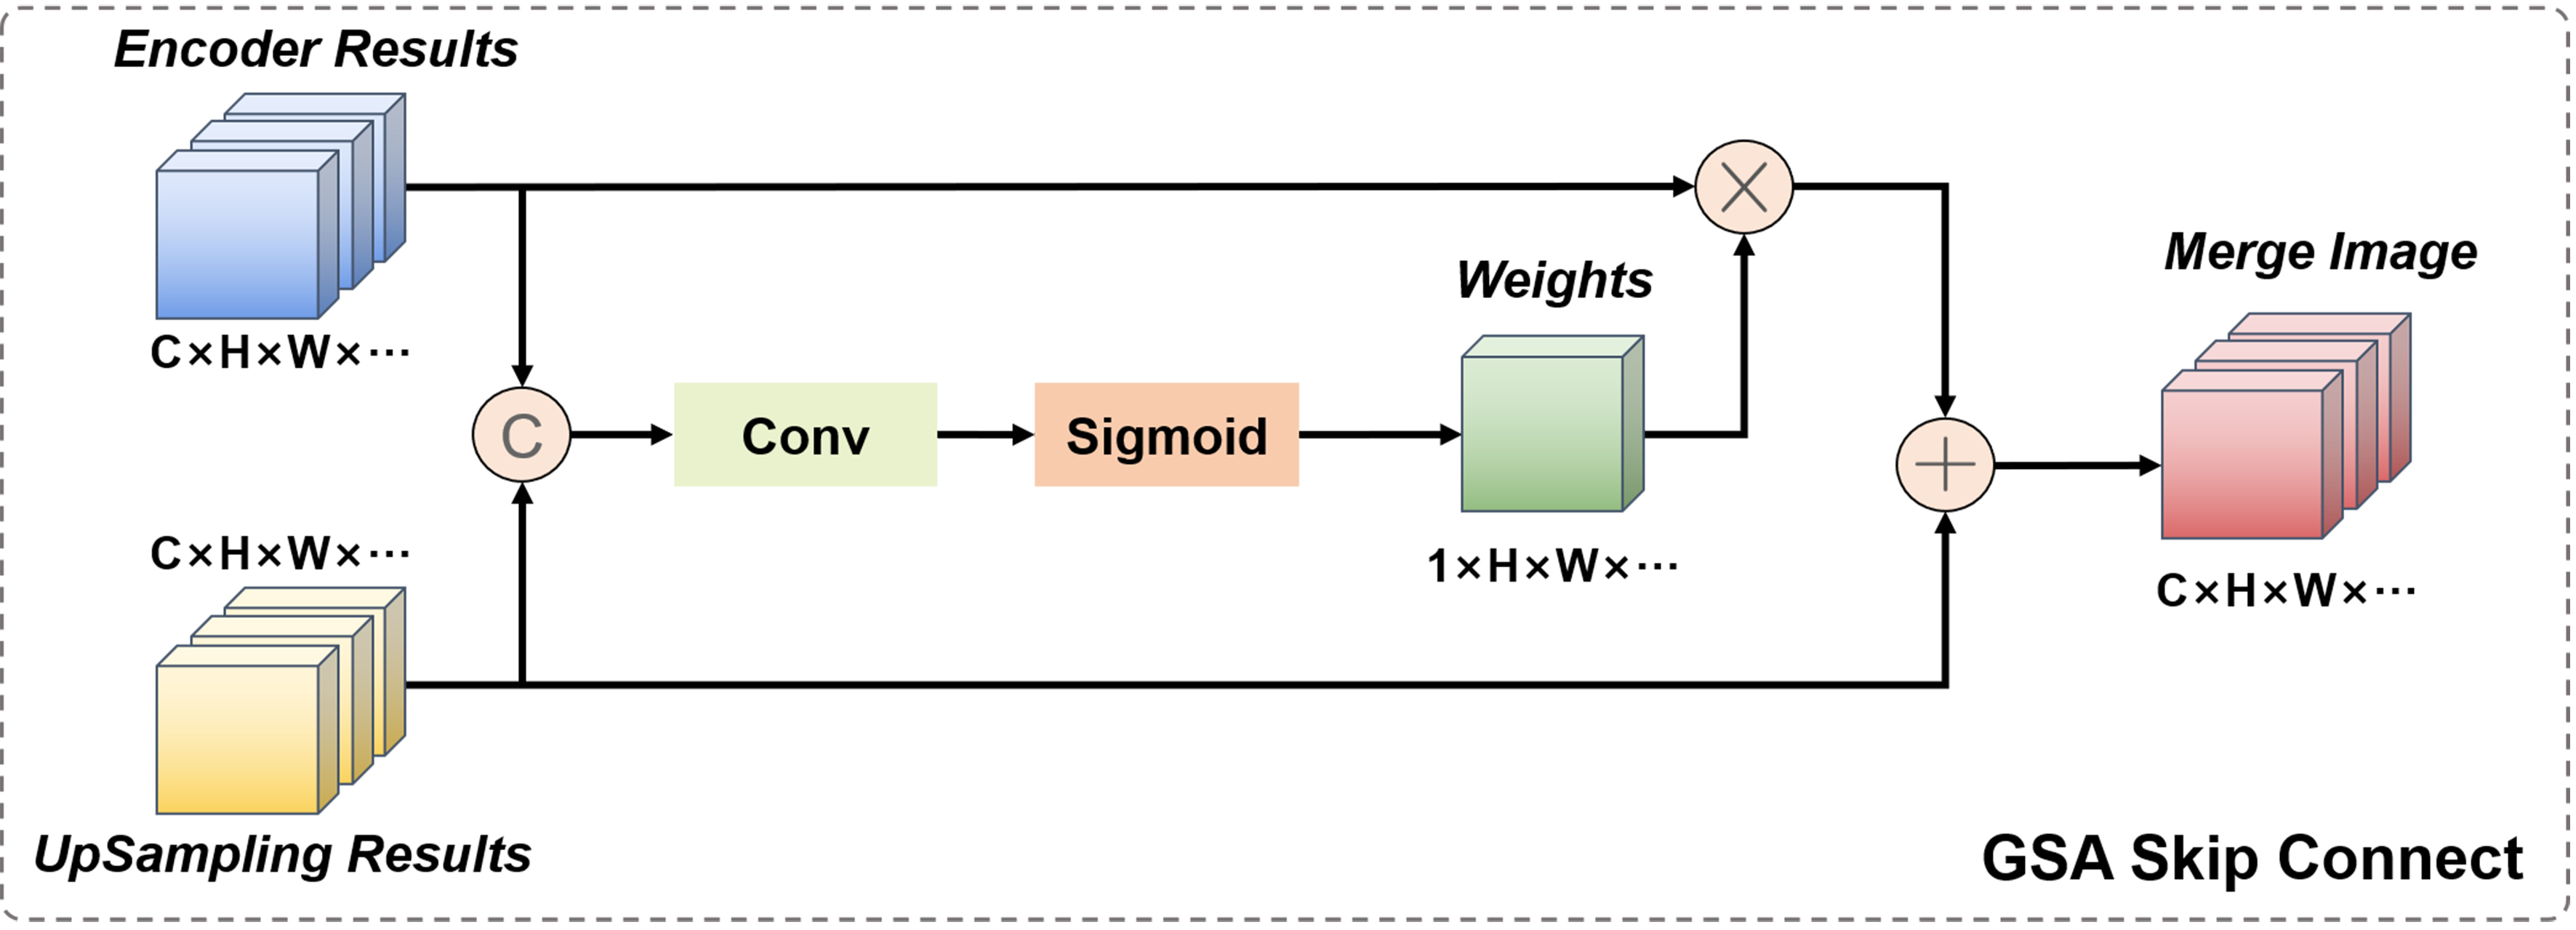

For the network, the skip connection mechanism and the bottleneck layer are also important units. Here, we have made improvements to these two units by proposing a skip connection fusion mechanism based on gated spatial attention (GSA) and a bottleneck layer based on axial attention. However, the only effective mechanism in practice is the skip connection fusion mechanism, which will be introduced in later experiments.

In the classic U-Net network model, the role of the skip connection layer is to fuse the low-level feature information of the encoder and the high-level semantic information of the decoder at the same resolution to ensure feature reusability, and to help the decoder stage recover the original pixel information of the up-sampled image, usually using channel concatenation for fusion. However, for 3D and even higher-dimensional images containing other information, the computational cost of channel concatenation cannot be ignored. Therefore, in medical images, the commonly used skip connection fusion strategy adopts the point-wise addition operation. It should be noted that although point-wise addition can reduce computation, this direct summation of high-level semantic information and low-level feature information without distinction may disrupt the coherence of the original semantic information, thereby reducing the reliability of the network. Therefore, here we propose a skip connection fusion strategy based on GSA, as shown in Figure 5.

This module combines the output image of the encoder part and the up-sampled image of the decoder part. Firstly, the two are concatenated in the channel dimension, and then the concatenated result is jointly fed into a regular convolution with a kernel size of 1. The output is a convolution result with 1 channel and a size equal to the input image size, which is activated by the Sigmoid function to become the spatial attention weight of the encoder image. This weight combines the information of low-level feature images and high-level semantic images, and is a learnable dynamically adjustable fusion weight. Finally, by weighting the encoder image and adding it point by point to the decoder image, the semantic coherence of the fused image is ensured.